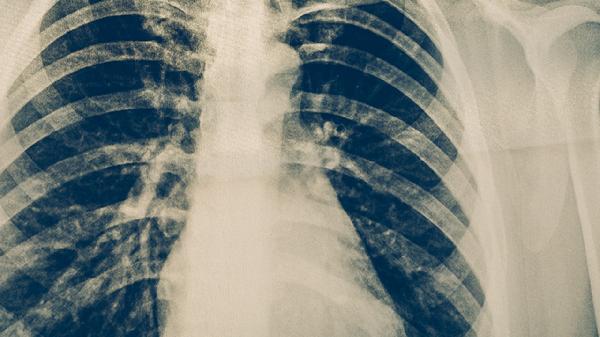

肺结核的治疗强调早期、联合、适量、规律和全程用药,患者切不可自行停药或更改剂量,以免导致治疗失败或产生耐药。在药物治疗期间,应保证充足的营养支持,多摄入富含优质蛋白和维生素的食物,如鸡蛋、牛奶、瘦肉和新鲜蔬菜水果,以帮助身体恢复。同时,应注意休息,避免劳累,保持居住环境通风,做好呼吸道隔离,防止疾病传播。定期复查胸部影像学和痰菌检查对于评估疗效至关重要。任何用药方案的调整都必须由专科医生根据病情决定。